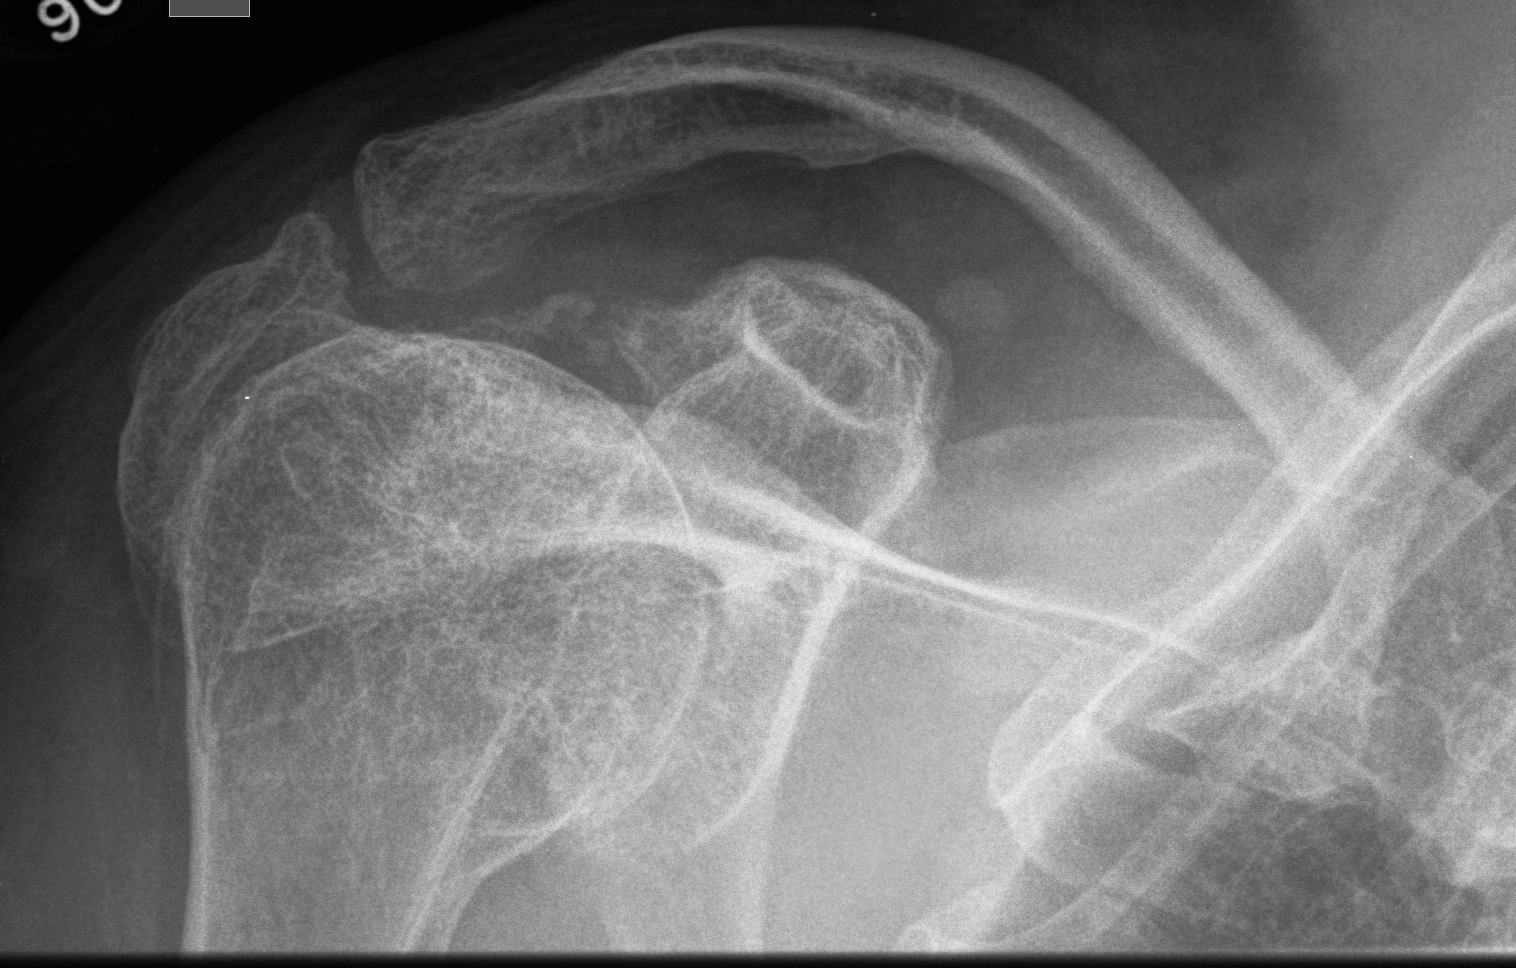

Basilar impression / invagination

Very serious problem

- the foramen magnum invaginating into the posterior fossa

- leads to stenosis with resultant hydrocephalus

- compression of the cerebellum, brain stem, and cervical cord

Lateral cervical spine radiograph

- upward migration of the cervical spine into the base of the skull

- deformity may be subtle and requires careful scrutiny of the radiographs

Various descriptions of the characteristic skull shape

- Darth Vader